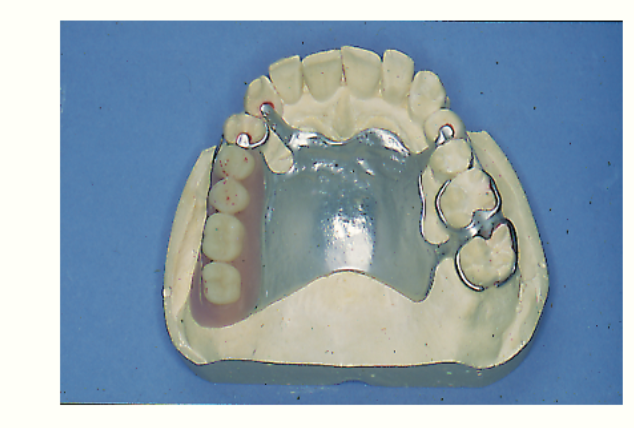

what type of denture is this

A

Class II